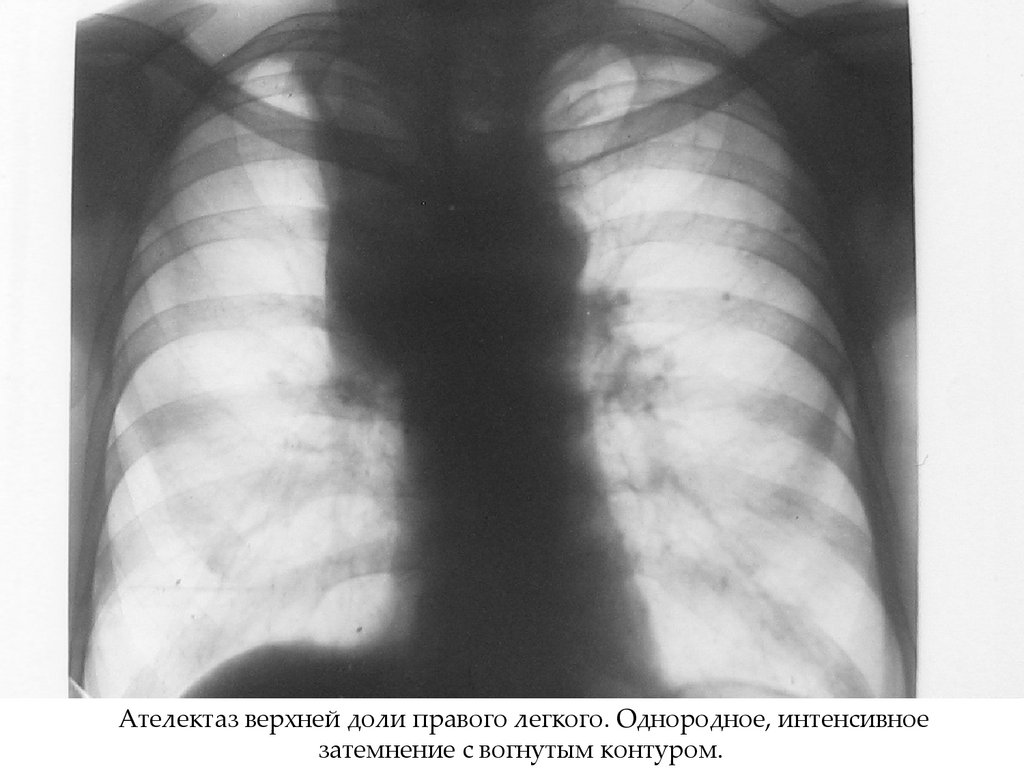

38. 3 стадия – ателектаз - полная непроходимость

Рентгенологическая картина:

• Интенсивное гомогенное затемнение

треугольной формы с вогнутыми контурами

• При ателектазе доли, легкого – смещение

органов средостения в сторону поражения.

Ателектаз верхней доли правого легкого. Однородное, интенсивное

затемнение с вогнутым контуром.